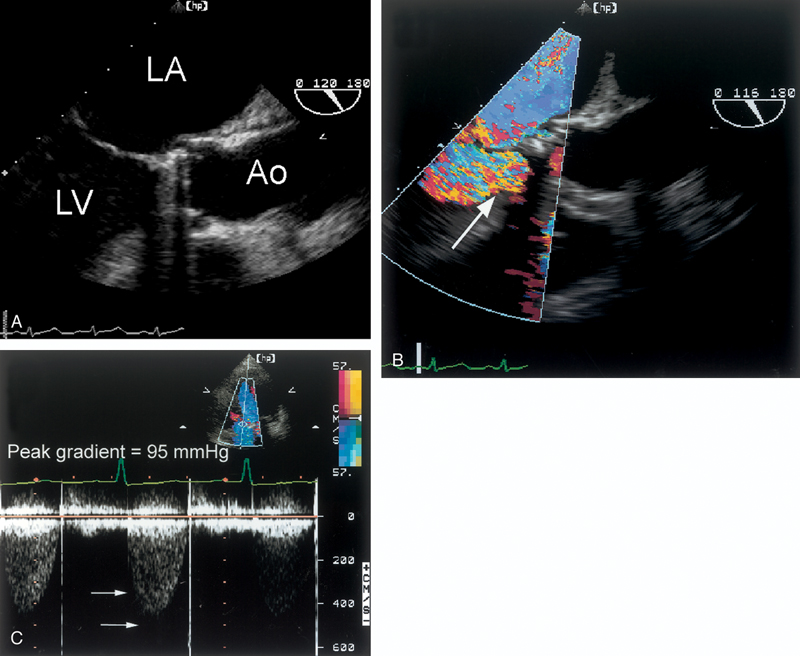

فحوصات تشخيصية لبعض امراض القلب والشرايين التاجية